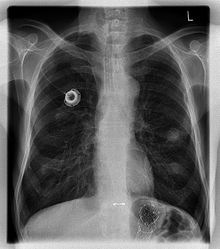

The image below is a chest X-ray of a patient with a port device. The reservoir is located on the right mid-clavicular line in the 4th intercostal space. The catheter can be seen running laterally from the reservoir toward the right axillary vein, and then curving back around medially to follow the right subclavian vein to the right brachiocephalic vein, finally ending in the SVC just outside the right atrium.

Image courtesy of Pixman